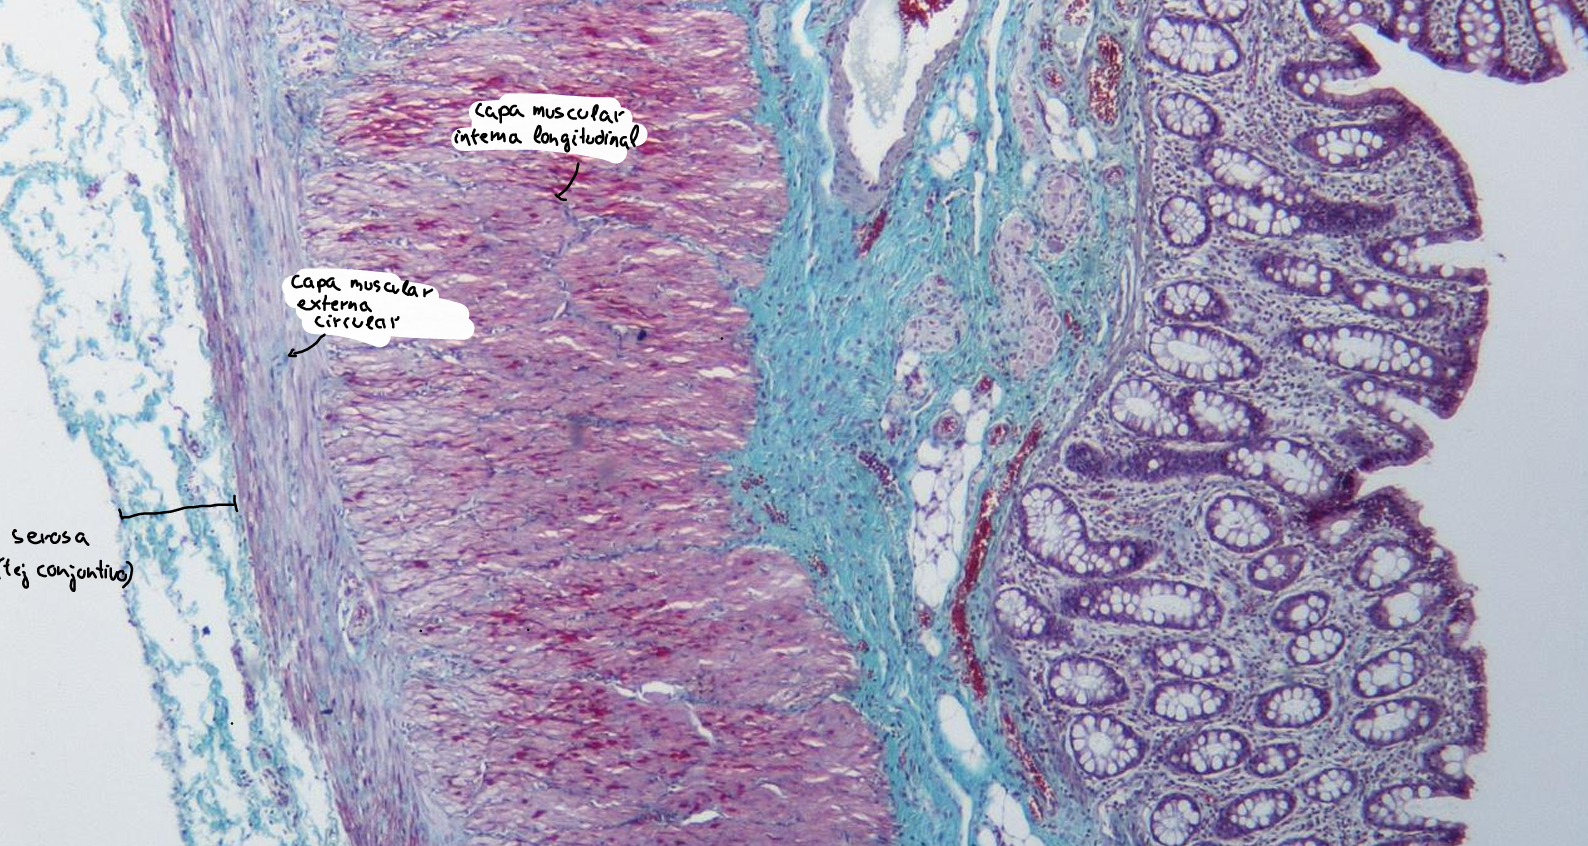

intestino grueso es la parte final del sistema digestivo, encargada de absorber agua y electrolitos, además de formar y eliminar las heces.